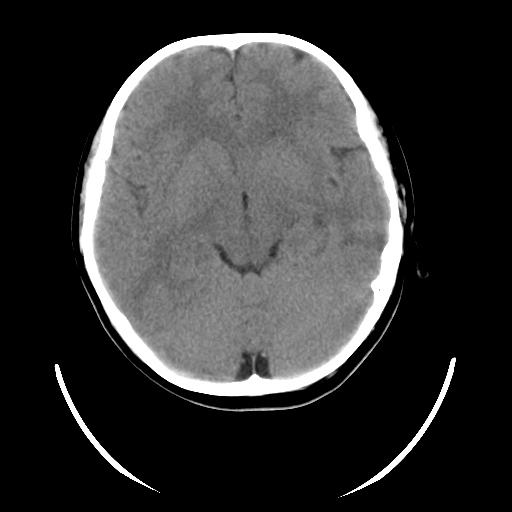

女,6岁,头痛、呕吐一天。

颅脑ct平扫未见明显异常。

头颅ct平扫未见明确异常,随诊复查。